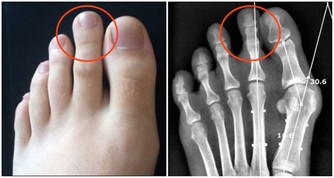

中醫講:“腎主骨,骨升髓”,生氣多時會導致骨痛,肢體麻木,關節炎等。